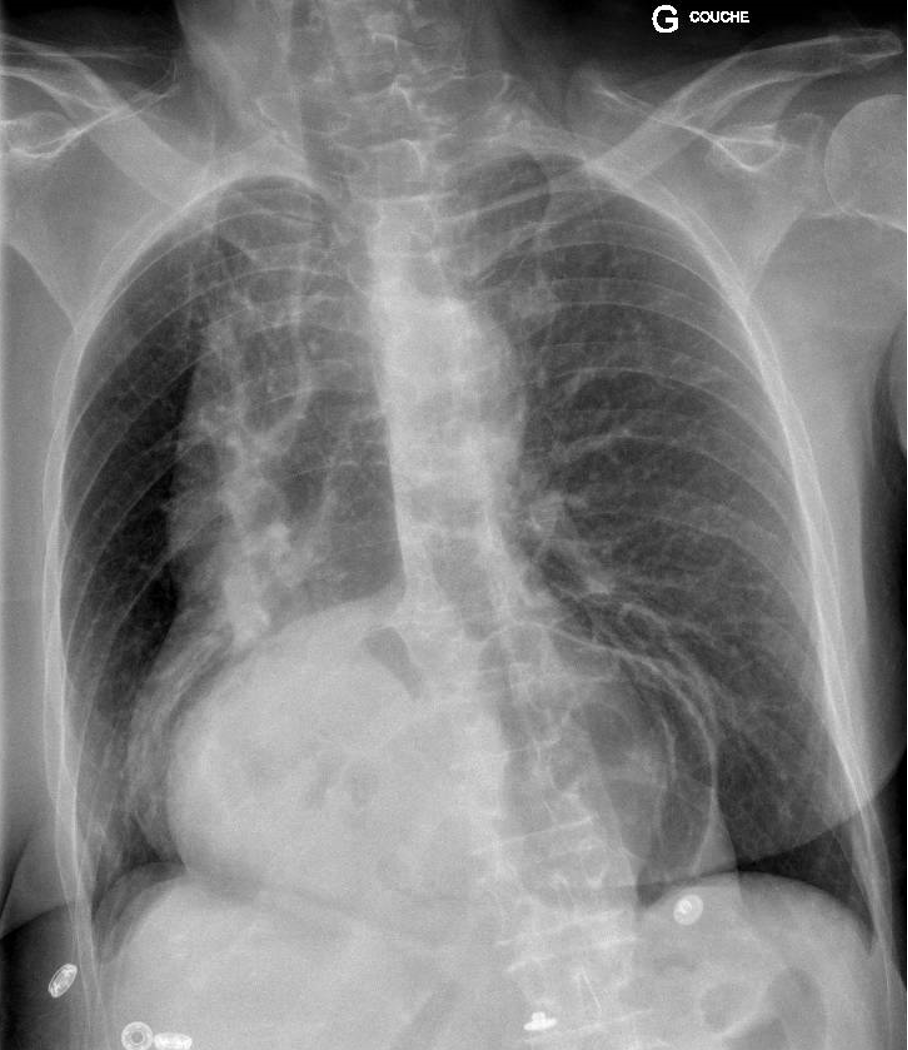

Tu prends en charge un patient de 60 ans, connu pour une BPCO de stade 2A selon GOLD, qui présente une dyspnée nouvelle, sans autres plaintes. Le status montre une légère tachypnée, sans utilisation de la musculature accessoire, avec une auscultation pulmonaire lointaine et qui nécessite 2L/min d'oxygénothérapie. Le status cardio-vasculaire et neurologique sont dans la norme.

Voici sa radiographie du thorax :

Que fais-tu ensuite ?